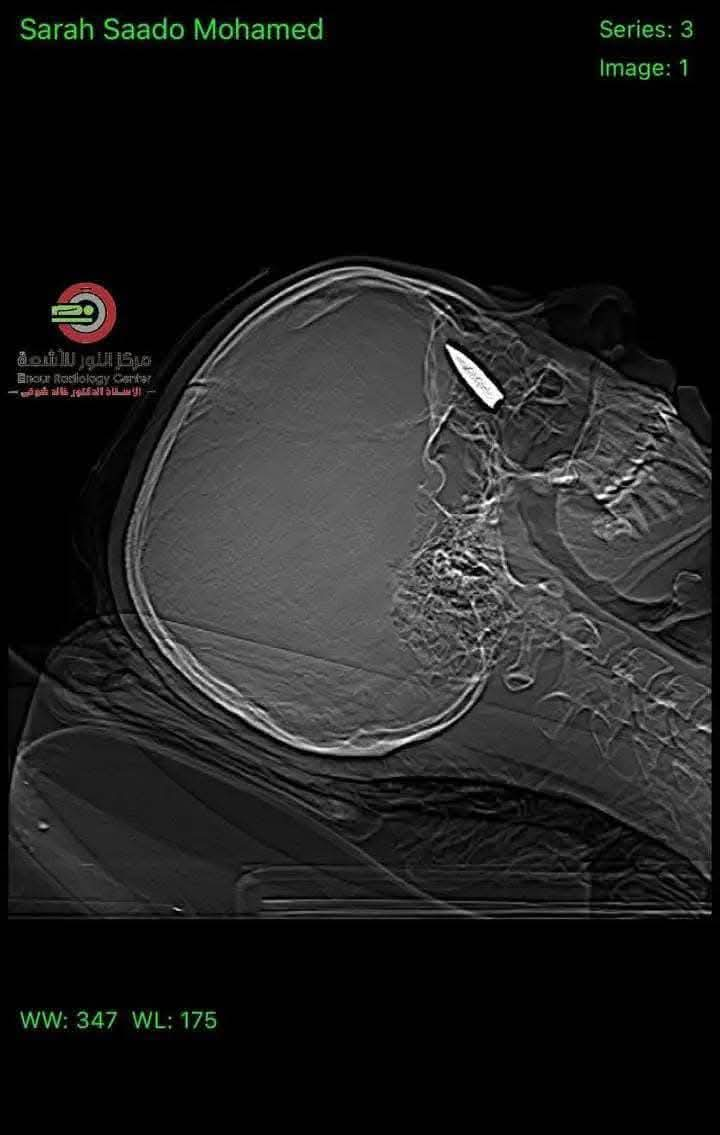

القاهرة - في إنجاز طبي استثنائي، نجح فريق جراحي في مركز الفردوس للعيون بجمهورية مصر العربية، بقيادة الدكتور المصري أحمد توفيق والدكتور مصطفى عبد الله، في إجراء عملية جراحية معقدة لإزالة طلق ناري استقر خلف عين شابة فلسطينية.

وكانت الشابة قد أصيبت خلال نزوحها في منطقة النصيرات بطلق ناري أُطلق من طائرة كواد كابتر، ما أدى إلى اختراق الجمجمة واستقرار الرصاصة في منطقة حساسة خلف العين. وبعد تحويلها للعلاج في مصر، خضعت للعملية الدقيقة التي وصفها الأطباء بأنها "معجزة طبية" نظرًا لحساسية موقع الطلق والمخاطر المحتملة.

وأكد الفريق الطبي أن العملية تكللت بالنجاح، حيث تم استخراج الرصاصة دون إحداث أضرار بالغة، مشيرين إلى أن حالة الشابة مستقرة حاليًا وتخضع للمتابعة الطبية الدقيقة.